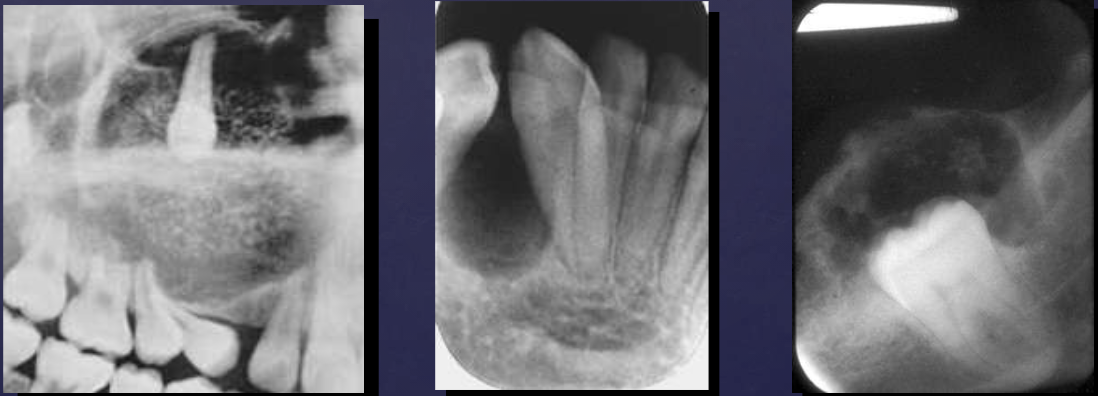

describe what’s occurring in this radiograph

pericoronal/mural; impacted tooth

displacement of #32 + IAN

osseous expansion

thinning of cortices

describe the ameloblastoma in this radiograph

multilocular w/ coarse septae

thinning of inferior mand border

displacement of teeth + IAN